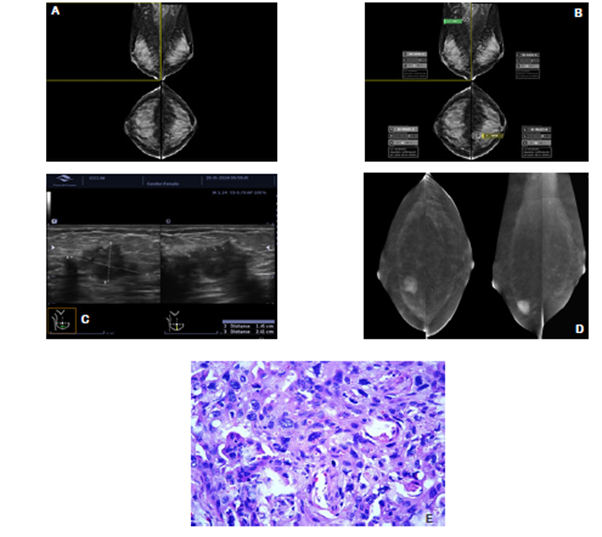

En los últimos años, el uso de algoritmos de inteligencia artificial (IA) en la evaluación de mamografías ha ganado una atención significativa.5,6 Estos algoritmos tienen el potencial de mejorar la precisión y la eficiencia de la detección del cáncer de mama al ayudar a los radiólogos en la detección y clasificación de lesiones sospechosas, esto puede ayudar a reducir la carga de trabajo de los radiólogos al automatizar el proceso de detección inicial, lo que les permite centrarse en casos más complejos. Varios estudios han demostrado la capacidad de los algoritmos de IA para superar a los radiólogos humanos en la detección y clasificación de la densidad y las lesiones mamarias, con mayores tasas de sensibilidad y especificidad (Figura 1A-B y Figura 2A-B). Por ejemplo, Logan et al. publicaron en 2023 pasado una revisión exhaustiva de la literatura sobre el algoritmo de aprendizaje profundo, a través de su aplicación fue capaz de lograr una sensibilidad del 90% y una especificidad del 85% en la detección del cáncer de mama, en comparación con el rendimiento promedio del radiólogo de 77% de sensibilidad y 79% de especificidad.5 Además, estos algoritmos aún necesitan información de entrada para seguir optimizando su ya alto rendimiento (Figura 2 C-D).

Figura 1 A. Paciente de 48 años con una masa palpable en el cuadrante inferior de su mama derecha. 1.B. El algoritmo de IA identifica la lesión como altamente sugestiva de malignidad. 1.C. En la ecografía, una masa sólida irregular altamente sospechosa. Centro Clínico de la Mama - CECLIM, Caracas - Venezuela. Work station for mammography, DIARM DM™, y brAInray™, Artificial Inteligence for Mammography, USA, 2024, http://www.medicalscientific.com/